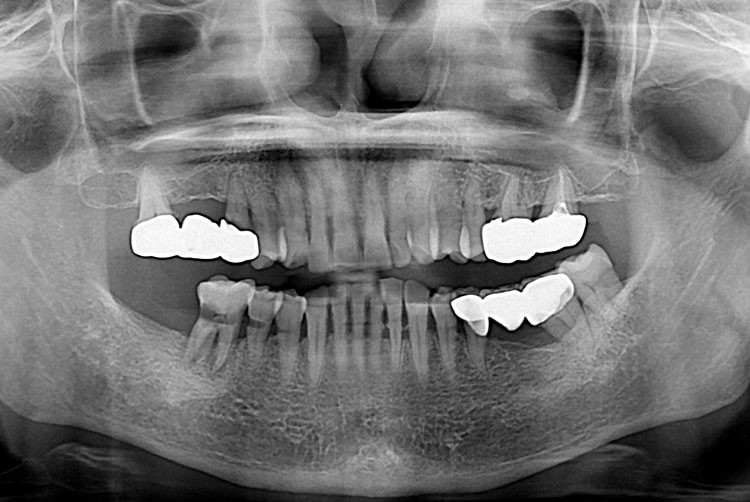

[임플란트] 임플란트

치료전 : 2017-01-12

세종치과는 많은 환자와 다양한 케이스를 바탕으로 항상 편안한 임플란트 수술을 제공하고자 노력하고,

오래동안 튼튼히 쓸 수 있는 임플란트 수술을 가장 큰 목표로 삼고 있습니다.